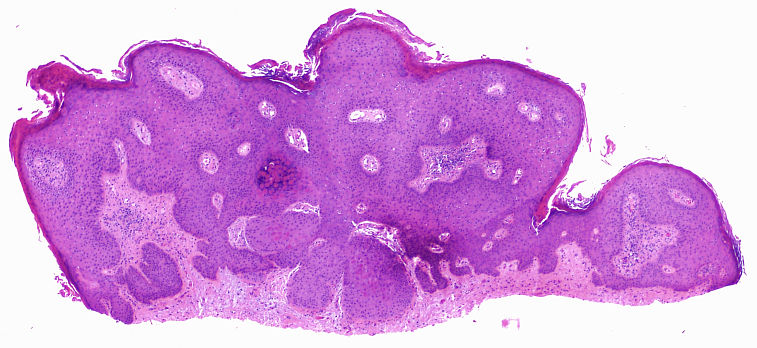

Cas dermatopaotologia. Dona de 36 anys amb pàpules pruriginoses vulvars

Juny 2013